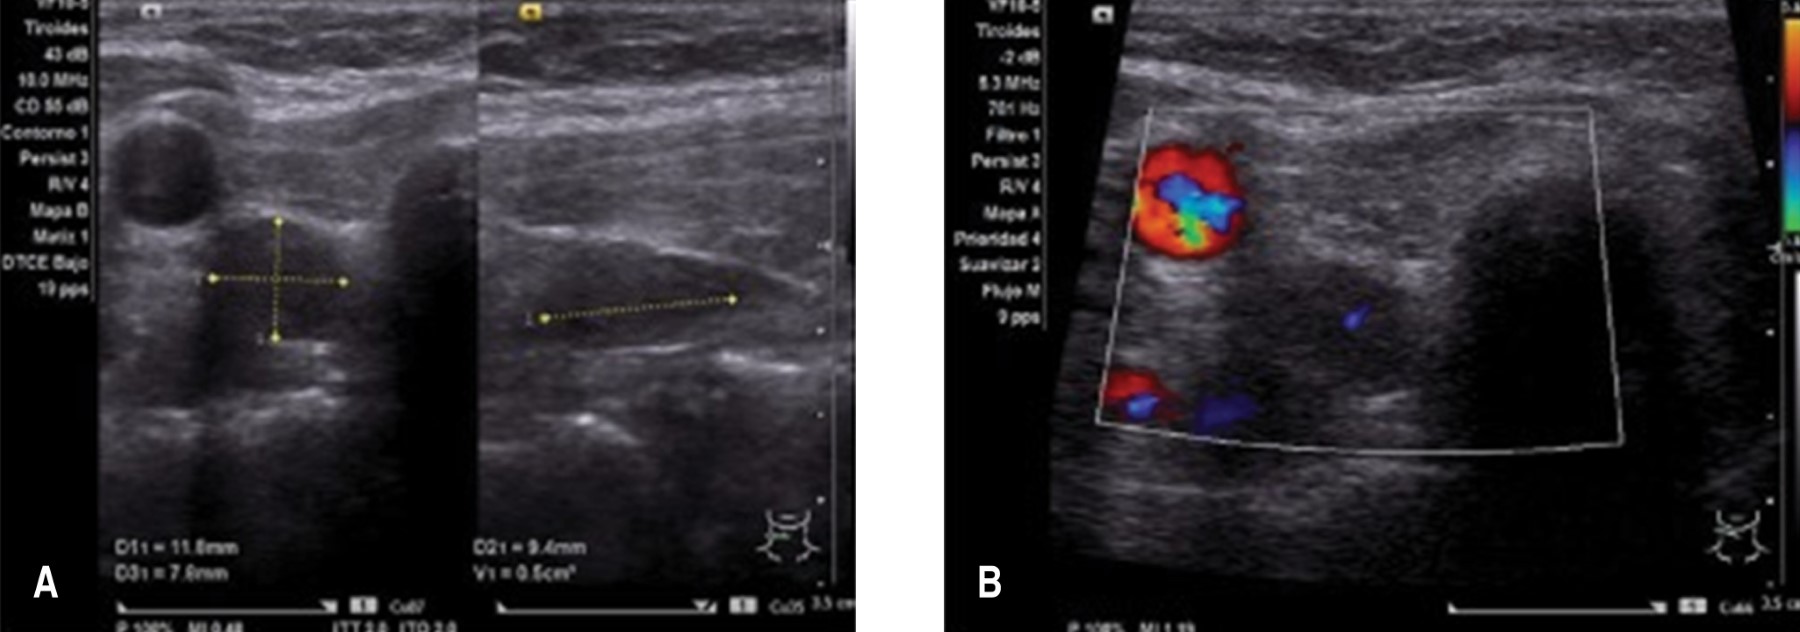

Introduction: There are few reported cases of acute pancreatitis secondary to primary hyperparathyroidism in children. Clinical case: Nine-year-old male patient with significant obesity. His current condition of four days of evolution, with abdominal pain in the epigastrium that progressively increased in intensity. Upon admission, the patient was seriously ill. Pancreatitis was confirmed by laboratory results (lipase 1.805 U/L, amylase 784 U/L) and abdominal tomography (cyst and necrosis of the pancreas). Serum calcium was persistently elevated. Primary hyperparathyroidism was diagnosed by elevated levels of parathyroid hormone (314.4 pg/dL) and parathyroid adenoma identified in ultrasound. Conclusions: Primary hyperparathyroidism should be one of the possible causes of pancreatitis in children, particularly when hypercalcemia is detected.

Figure 1

Figure 2